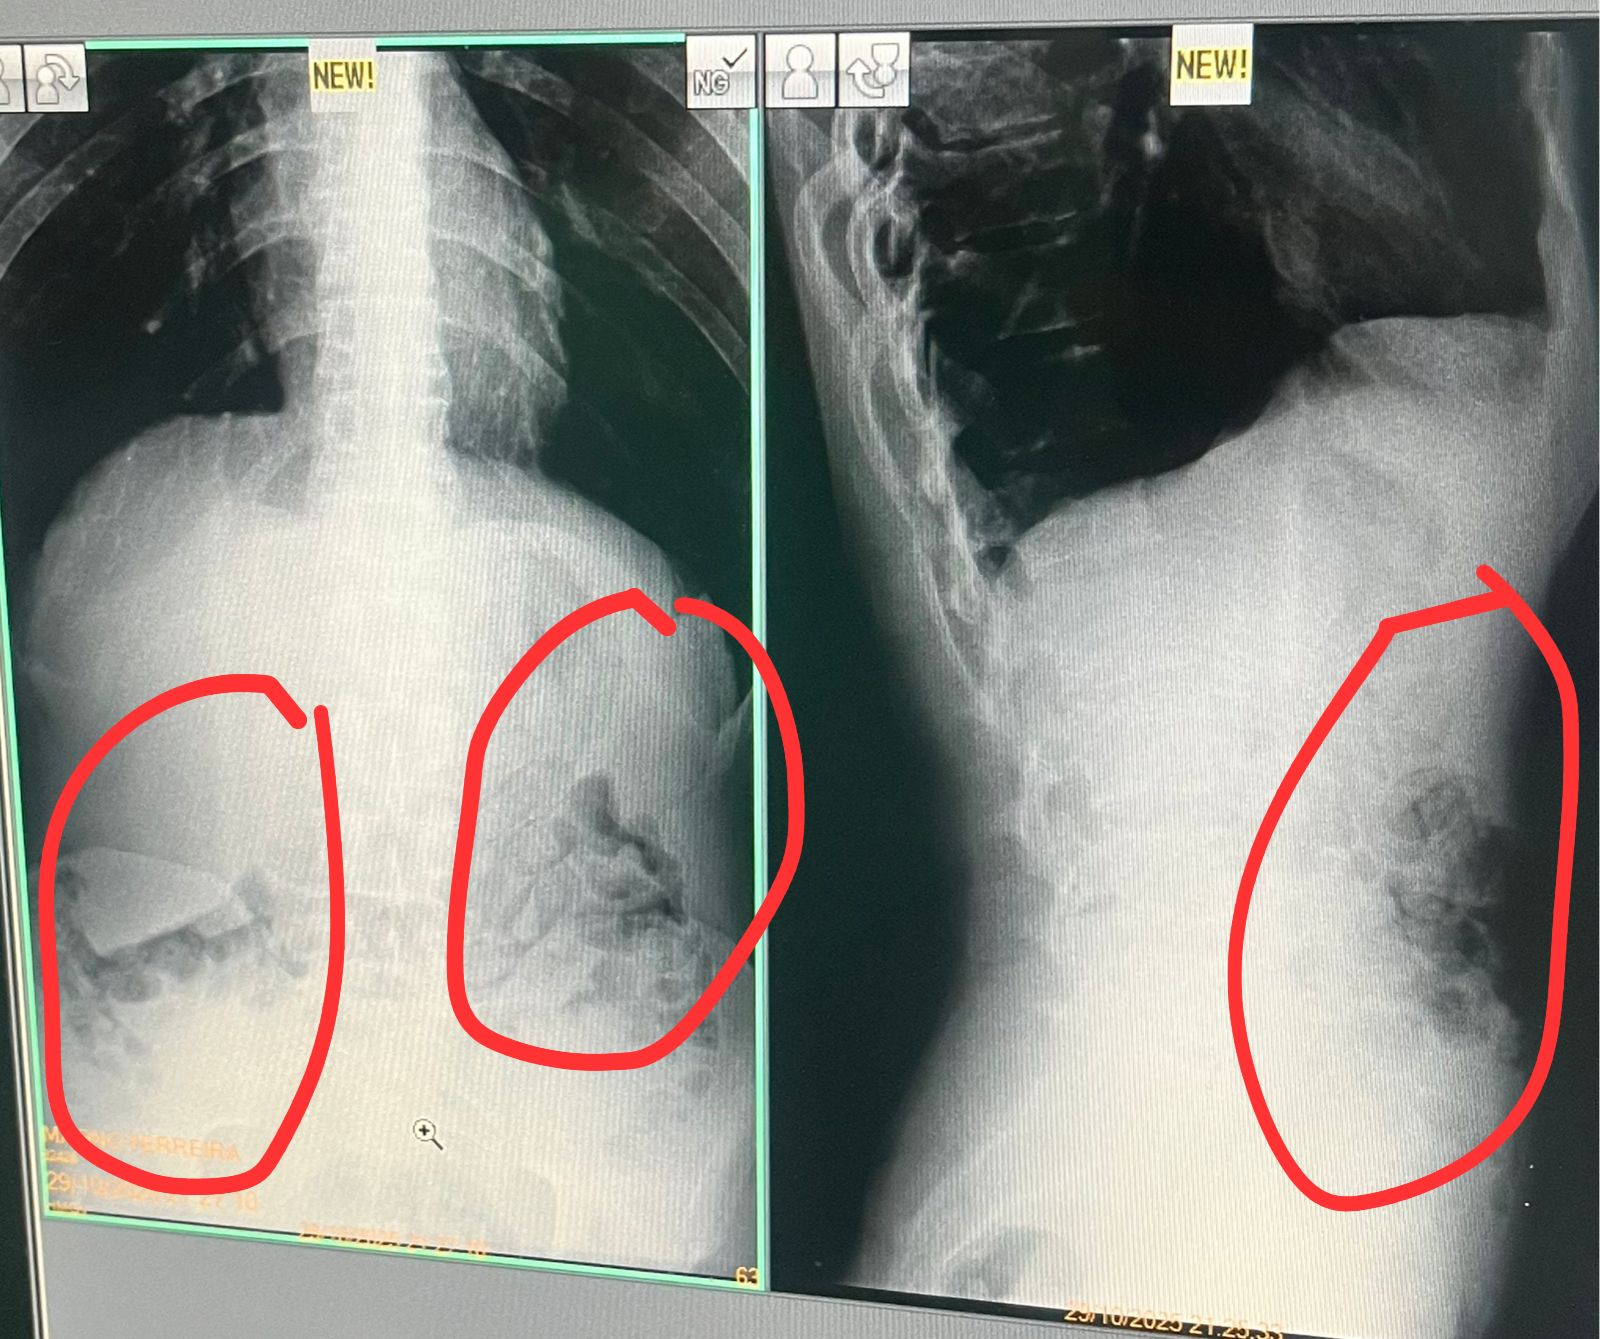

Os sete detentos foram levados ao setor de segurança do presídio e, posteriormente, ao Hospital Regional, onde exames de raio-X revelaram que cinco deles haviam engolido invólucros, compatíveis com os encontrados no banheiro.